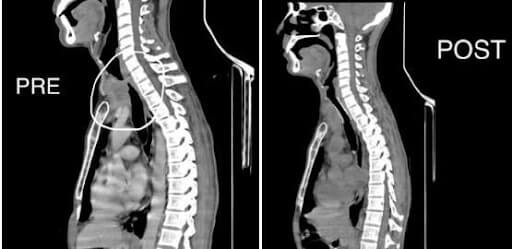

A 47-year-old man came to the OPD with a trachea narrowed by more than 90%.

The condition stemmed from thyroid extending to the trachea. A self-expanding metallic stent was successfully placed in the patient’s airway to help him breathe well. The patient was able to breathe well after the procedure.